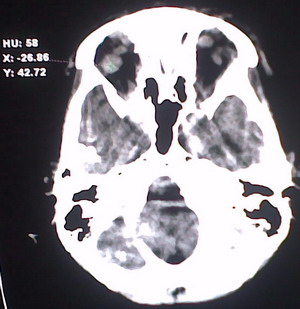

以下是引用jiajie在2009-2-3 20:02:00的发言:[br]脑室周围白质区可见大量斑片状钙化,部分融合成带状,双侧侧脑室及第三脑室扩大。[br]考虑弓形体原虫感染。(先天性宫内感染、torch综合症)

以下是引用lkc8963在2009-2-3 21:15:00的发言:[br]临床眼睑可见静脉扩张,ct双侧眼上静脉亦示扩张,颅内钙化以皮层\\软脑膜为主而不是位于白质和室管膜,再加上静脉窦异常,还是应该考虑静脉血管瘤病,可能为较复杂的血管畸形.

以下是引用卜一在2009-2-4 9:21:00的发言:[br]sturge-weber综合征:面部三叉神经分布区的毛细血管性或海绵状血管瘤以及同侧枕、顶或额叶软脑膜的血管瘤(以静脉性为主)。脑皮质,特别是第二三层,毛细血管可有增厚和钙化。局部发生层状坏死、神经细胞脱失、萎缩、胶质细胞增生及钙盐沉着。可根据面部典型分布的特征性皮痣作出诊断。头颅ct:发现面部血管瘤同侧的脑内病理钙化影,呈双层线条波浪形、脑回形或树枝形。本例支持:sturge-weber综合征![br]